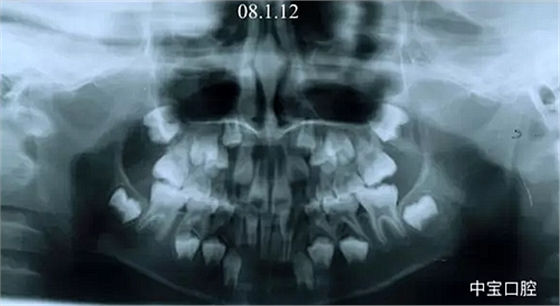

有一個(gè)七歲的小女孩,在替牙時(shí)媽媽發(fā)現(xiàn)孩子新長的牙不整齊,有一顆長到里面了,上下頜中線也不對稱,很著急就來到門診看牙。

經(jīng)過我臨床檢查和X線的診斷,決定早期干預(yù),每三個(gè)月定期復(fù)診檢查一次,并拔掉了幾個(gè)乳牙和四個(gè)恒牙,正畸專業(yè)叫序列拔牙。